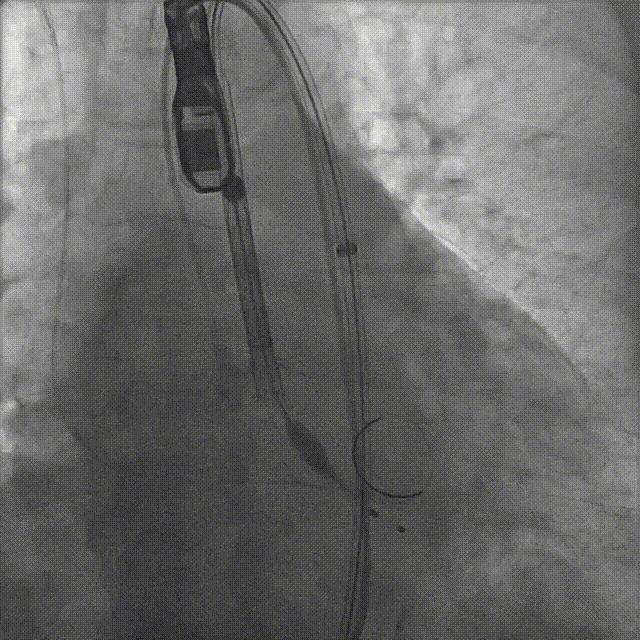

患者病史 体检发现心脏瓣膜病半月余,平素无症状 ,有高血压病史。 后来院复查诊断为:主动脉瓣狭窄(重度)、先天性主动脉瓣二叶瓣畸形、心室肥厚、升主动脉扩张心功能 I 级(NYHA 分级)、高血压病 2 级(极高危)。 术前 CT:Type0型二叶瓣,瓣叶增厚,无钙化,类风湿性;瓣环径25.6mm,LVOT稍收窄,瓣环水平夹角66.6°,轻微横位心;左右冠开口高度可,瓣叶不长,无冠脉风险;心室收缩末内径约32mm,室壁增厚;外周入路无明显迂曲,无钙化、双侧内径可、双股中分叉,右侧为主入路能够支持20F大鞘通过。 造影角度及入路:LAO 6° CAU 13° 手术策略 采用右侧股动脉为主入路,左侧为辅助入路,常规穿刺。推荐使用20球囊预扩,预装TAV29瓣膜,初始定位对齐瓣环上0mm开始释放。 手术过程 20号球囊预扩无明显腰征 输送器过弓跨瓣顺滑 80%工作位观察 术后造影,瓣膜释放位置良好,无瓣周漏 术后超声:人工生物瓣释放后形态满意,瓣叶开放、关闭活动良好,无瓣周漏;跨瓣血流速度降至 2.5m/s,平均压力梯度6mmHg,符合手术预期。 Prostyle A®预装干瓣——“刚柔并济”助力临床最优化解决方案: 丝滑过弓能力:Prostyle A®短瓣架设计联合远端超滑亲水涂层,即使没有联合使用snare,都可以柔顺过弓,该例横位心的患者更好的展现了输送系统的柔顺性; 平衡的径向支撑力:该例患者Type0型二叶瓣,术后形态展开良好且无瓣周漏,在横位心等复杂情况下实现稳定锚定。 80%可回收设计:80%工作位观察,起搏时间更短,对患者损伤减少到最小,也利于术中精准调整瓣膜位置,保证术后效果。